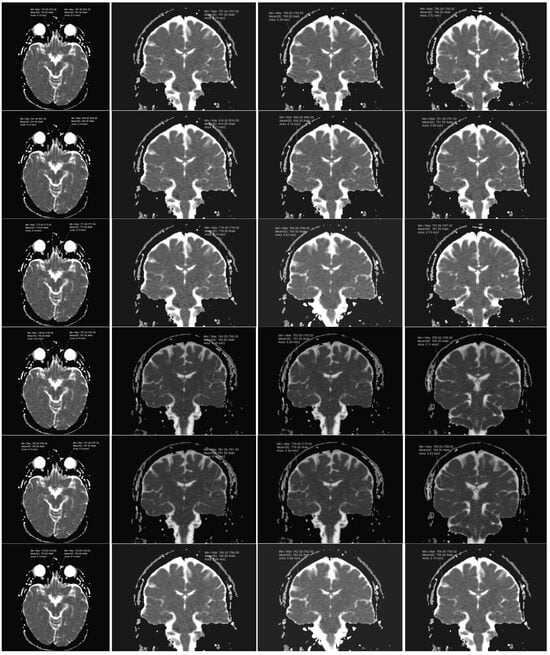

The olfactory bulbs (OBs), responsible for the smell perception, are situated on the bottom side of the brain, one above each nasal cavity. The gustatory cortex (GC), responsible for the perception of taste, consists of the anterior insula (AI) in the insular lobe with its extending anatomically associated overlying frontal–parietal operculum (FO-PO) [20]. (Figure 1).

Figure 1. Theoretical placing of ROIs in the following areas: olfactory bulbs (yellow), insular cortex (blue), frontal operculum (green), parietal operculum (red).